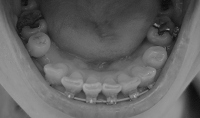

下のワイヤーは一番太いものになったので、今回の調整でキレイなアーチ状に揃ってくれるはず

順調なら、次回から抜歯痕を詰める作業にはいりますっ